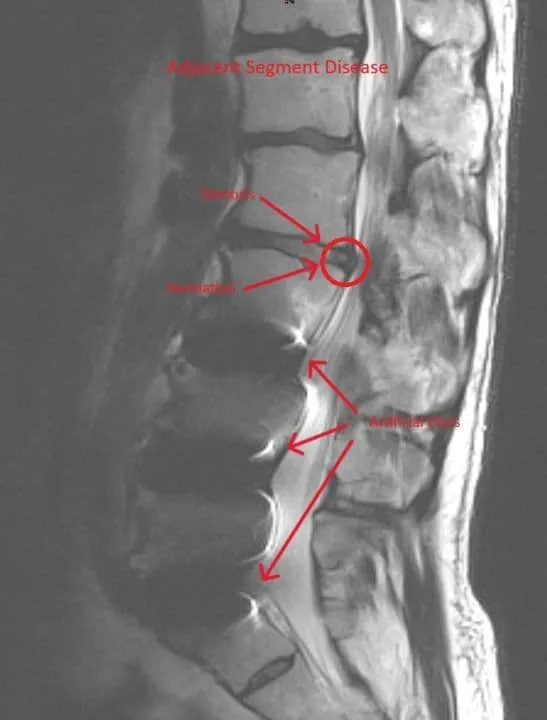

Stenosis Recurrence

Adjacent Segment Disease

MRI of lumbar spine showing recurrent disc herniation post discectomy highlighted by arrows.

Recurrent Herniation